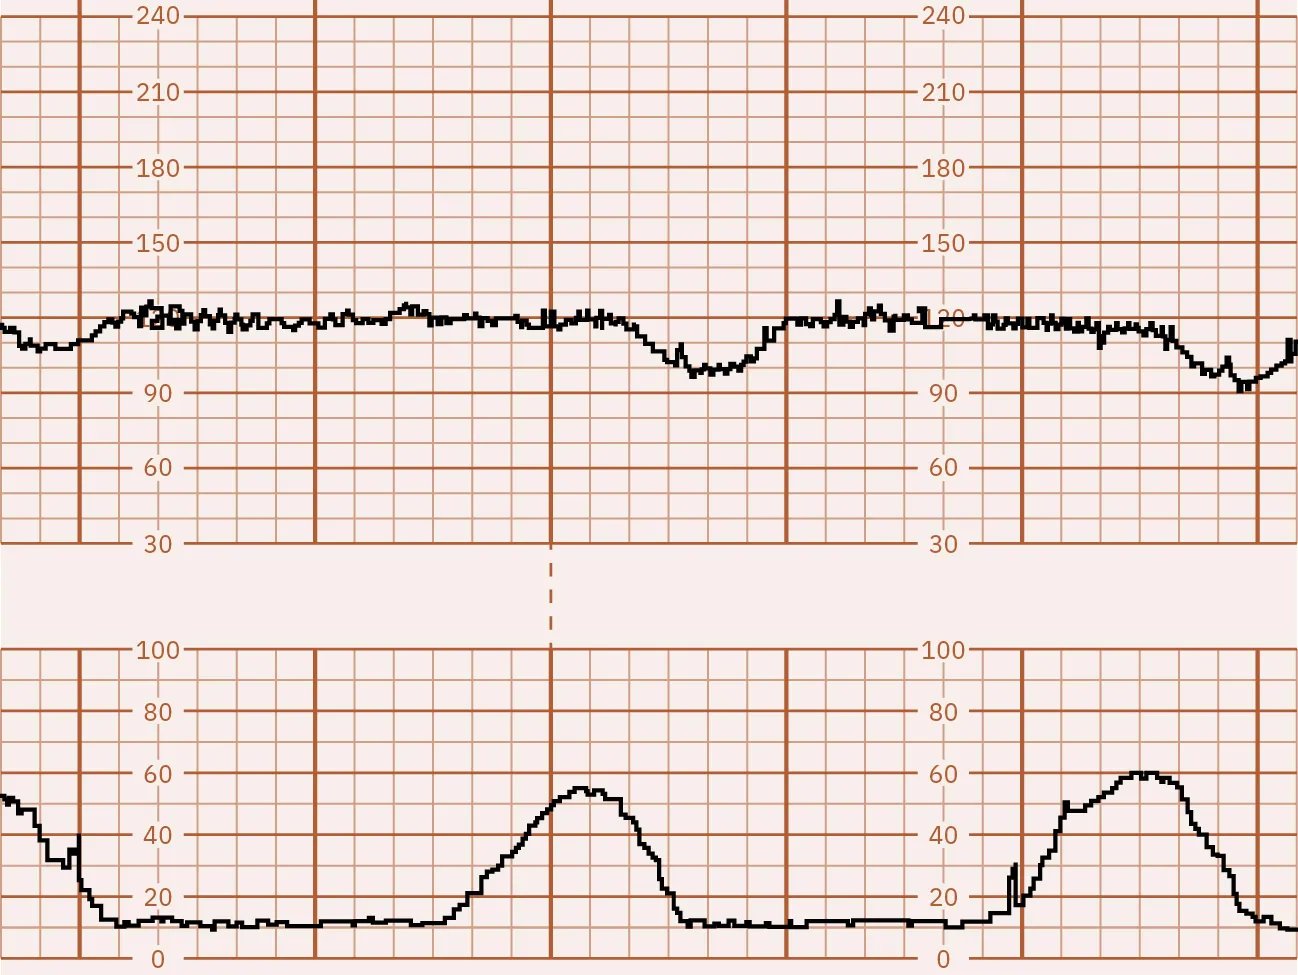

The CST test results are divided into several categories:

• Negative: This means there are no late or significant variable decelerations (Figure 13.11).

Fetal monitor tracing graphic depicting negative CST. Top strip remains stable during spikes in the lower strip.

Figure 13.11 Negative CST In this illustration, the FHR baseline is 130 and is at the top of the graph. Contractions are recorded on the bottom. This strip shows that with each contraction, or peak, at the bottom, the heart rate remains stable, which makes it a negative result. (attribution: Copyright Rice University, OpenStax, under CC BY 4.0 license)